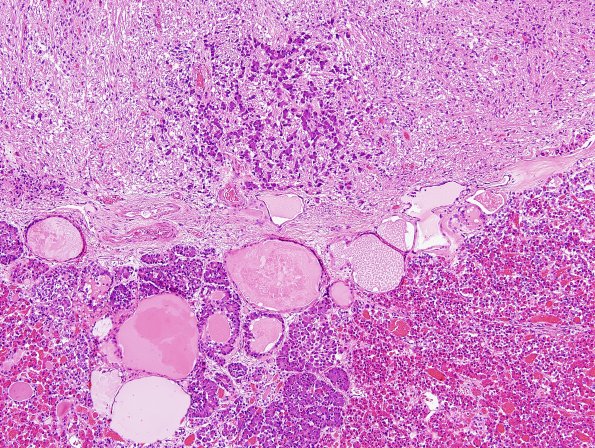

6E1-3 Another photogenic example of basophil invasion in the presence of intermediate lobe cysts. (H&E)